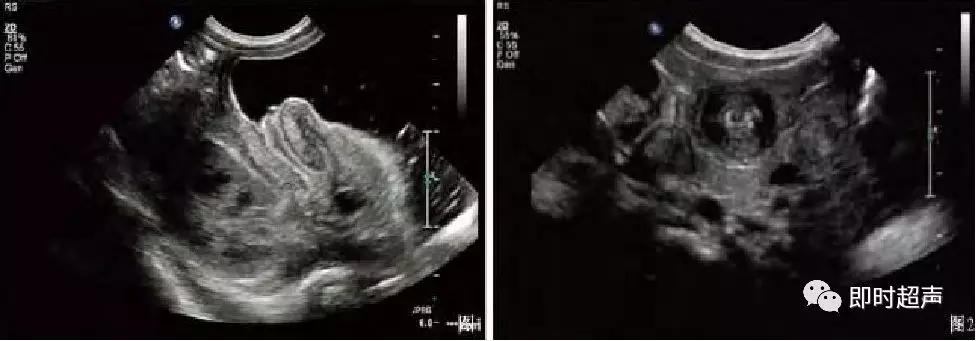

超声表现

低回声团:短轴 靶环征

长轴 套筒征

偏心 阑尾、息肉等

CDFI:局部血流信号增加

缺血坏死时血流信号消失

肠套叠超声表现

短轴切面同心圆征

长轴切面套筒征、短轴切面同心圆征